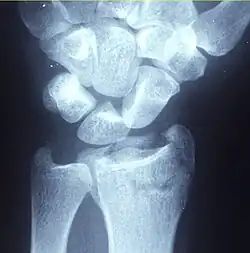

Diagnosis may be evident clinically when the distal radius is deformed, but should be confirmed by X-ray. The differential diagnosis includes scaphoid fractures and wrist dislocations, which can also co-exist with a distal radius fracture. Occasionally, fractures may not be seen on X-rays immediately after the injury. Delayed X-rays, X-ray computed tomography (CT scan), or Magnetic resonance imaging (MRI) can confirm the diagnosis.

X-ray of the affected wrist is required if a fracture is suspected. Posteroanterior, lateral, and oblique views can be used together to describe the fracture.[5] X-ray of the uninjured wrist should also be taken to determine if any normal anatomic variations exist before surgery.[5]

A CT scan is often performed to further investigate the articular anatomy of the fracture, especially for fracture and displacement within the distal radio-ulnar joint.[5]